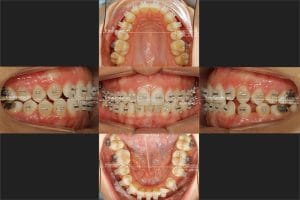

La paciente llevó el 2×4 (mirar la imagen de abajo) unos 6 meses, durante este tiempo empezó a recambiar sus dientes de leche gradualmente.

Una vez haya acabado el recambio dental se colocaron brackets mediante cementado directo en los demás dientes y se continuó con el tratamiento.